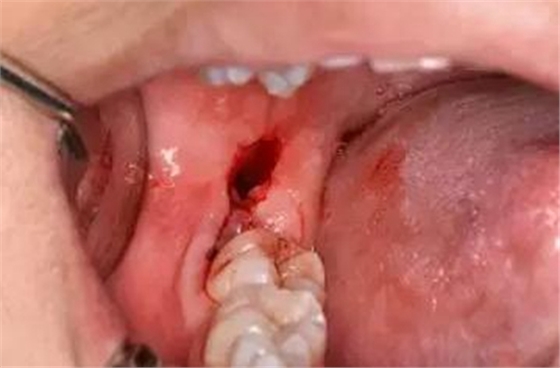

圖13.清理牙槽窩、對(duì)位傷口

圖14.僅在遠(yuǎn)中縫合兩針,不宜太緊。